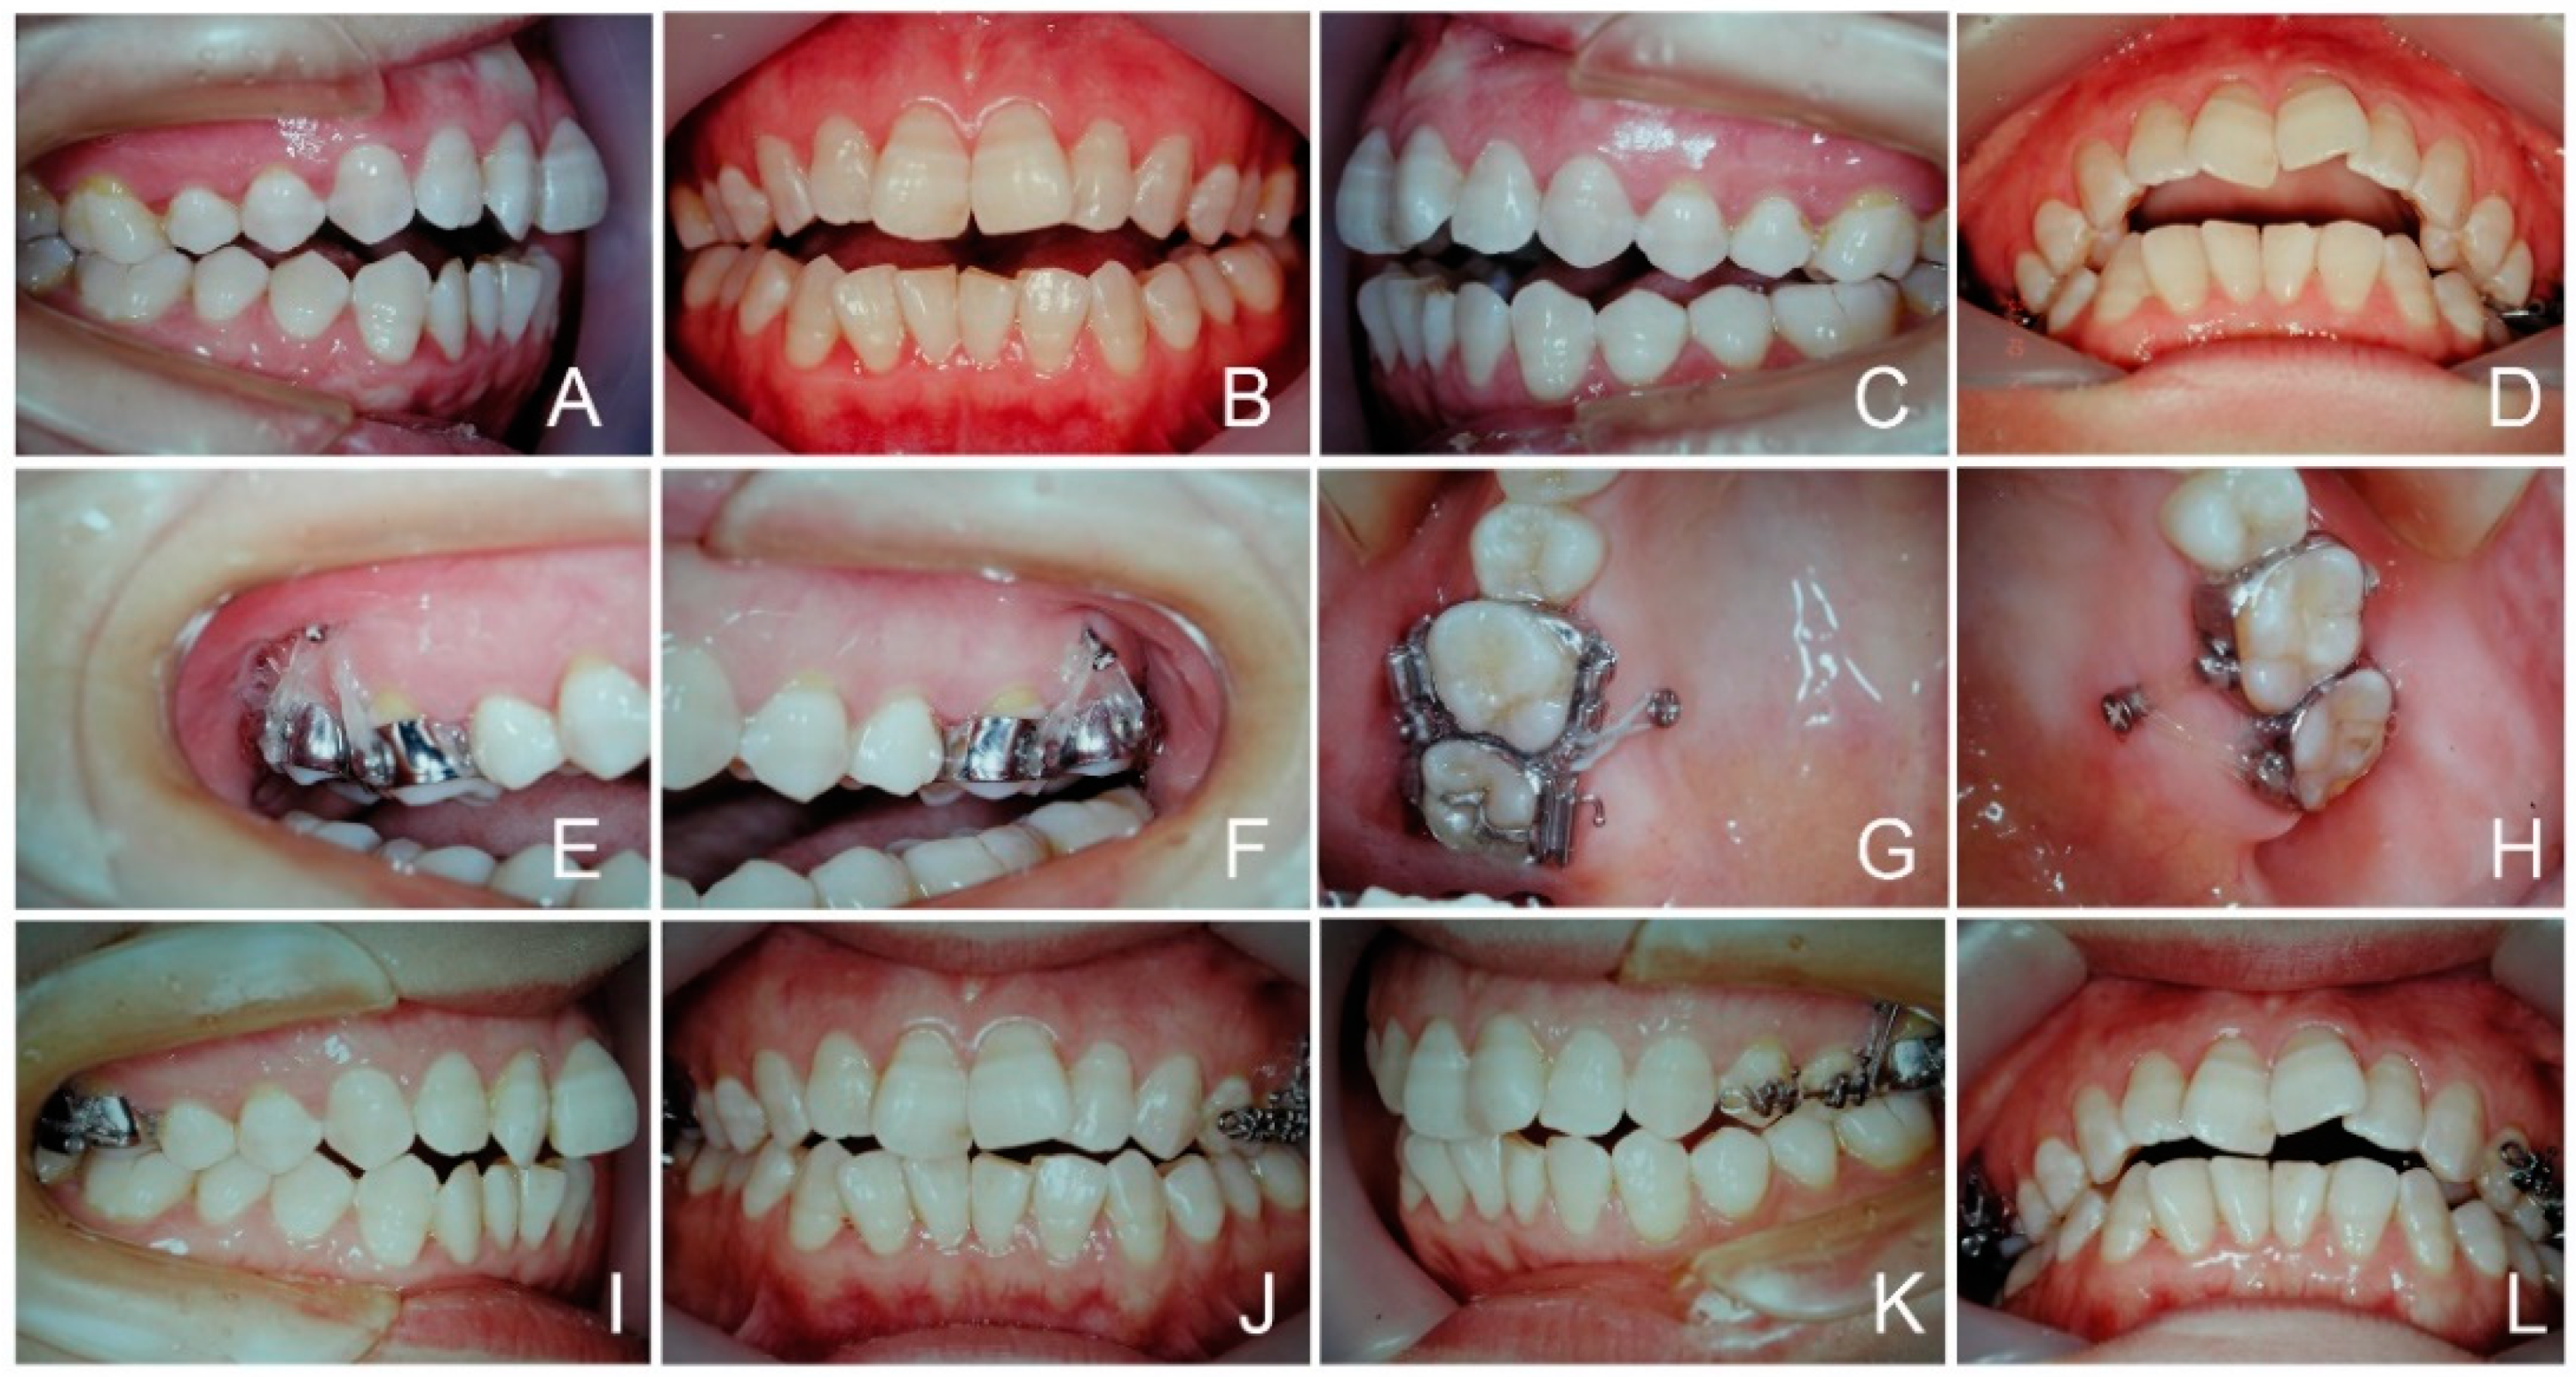

3.1. Case 3 (Posterior Intrusion, Figure 8 and Figure 9)